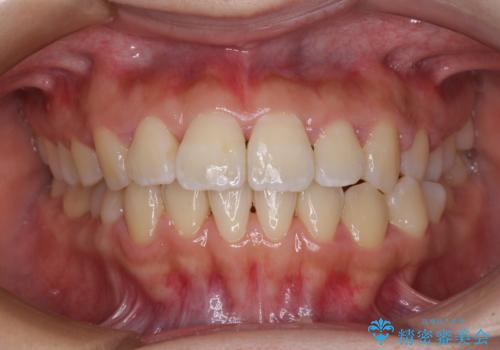

先天欠損のある歯列 インビザライン矯正

- 上顎前歯の突出感を気にして来院された患者様です。

下顎前歯2本が先天欠損しており、上顎歯列に対して、下顎歯列がアンバランスに小さい状況でした。

左右上顎側切歯2本が矮小歯であるため、上顎の抜歯ではなく、IPR(歯と歯の間を削る)と歯列全体の後方移動によってバランスを整えることとしました。

歯列のバランスが悪く、インビザライン矯正特有の奥歯の噛みにくさがなかなか改善されず、治療期間が長期化してしまいました。